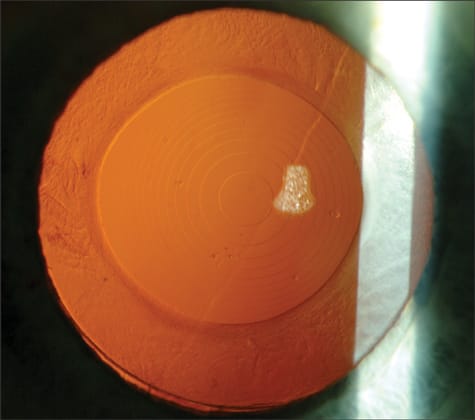

Figure 1. Slit-lamp photograph of a ReStor lens.

Figure 1. Image from a dissatisfied patient who had a Crystalens accommodating implant and then a YAG laser posterior capsulotomy (note pits) for early PCO.